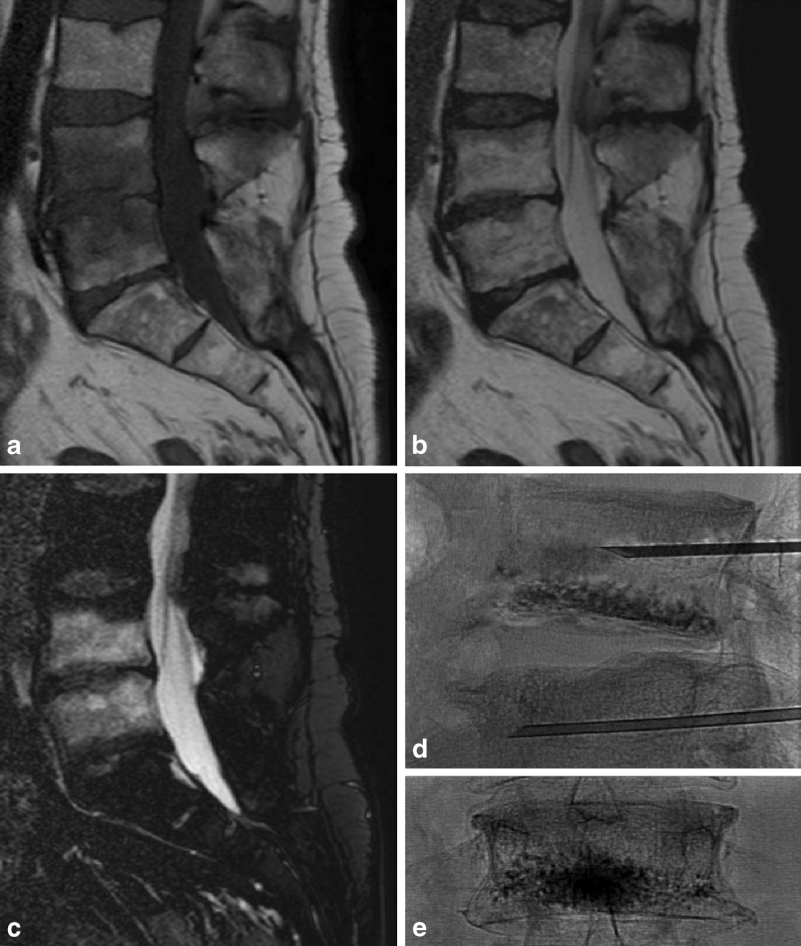

①吸收骨水泥的椎体增强术

a、b 和 c 提示 L4/5 椎体 Ⅰ 型 Modic 改变,d 提示 L4、L5 进行骨水泥注射的术中影像,e 提示术后复查 L4 椎体骨水泥填充情况。